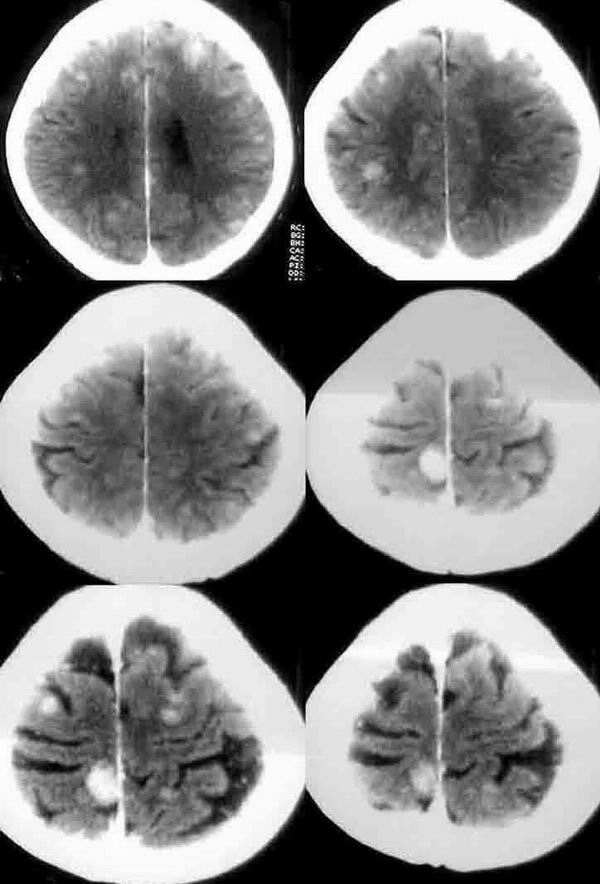

增强:脑内广泛多发结节影.多位于皮质和皮髓质交界区,强化明显.ct值达86.5hu.

要考虑转移瘤.因为病灶呈多个\"类园型\"肿块,并未见钙化灶,周围也无水肿带.

本例皮层及皮髓交界处的多发等高密度无水肿结节,考虑脑转移瘤可能性更大一些。

因为无水肿,而区别于结核肉芽肿,部分肺及骨的恶性肿瘤脑转移灶可无水肿,而无水肿的结核肉芽肿更少;结核肉芽肿多位于脑浅表部位,皮髓交界处很少见,而脑转移瘤更多位于此处(分水岭);结核肉芽肿平扫密度应更一致而非此例为等密度及稍高密度,增强扫描多为环形、结节形或不均匀强化,而非此例均匀性强化;结核性肉芽肿多伴有脑积水、脑梗塞,脑底池往往有较特征性的强化。

转移瘤可能性大,重点查甲状腺肾上腺等原发血供丰富的脏器.